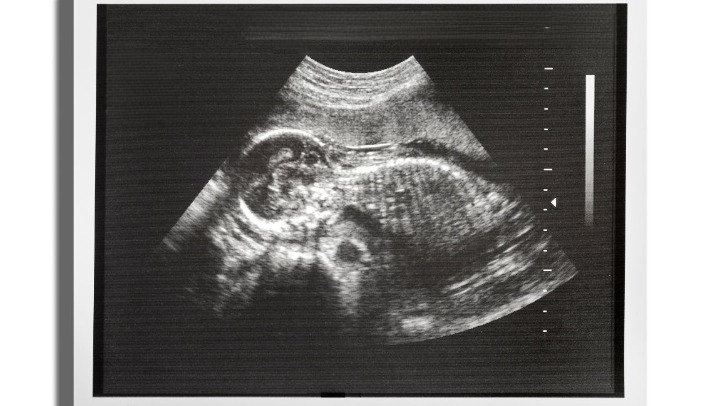

Pelvic ultrasound is often used to evaluate the reproductive organs in women, including the uterus and ovaries. It is commonly used in pregnancy to monitor fetal development, detect ectopic pregnancies, and diagnose conditions like ovarian cysts and uterine fibroids.

Ultrasound provides real-time imaging, which is particularly beneficial for procedures that require dynamic observation, such as guiding needle biopsies or monitoring fetal development during pregnancy.